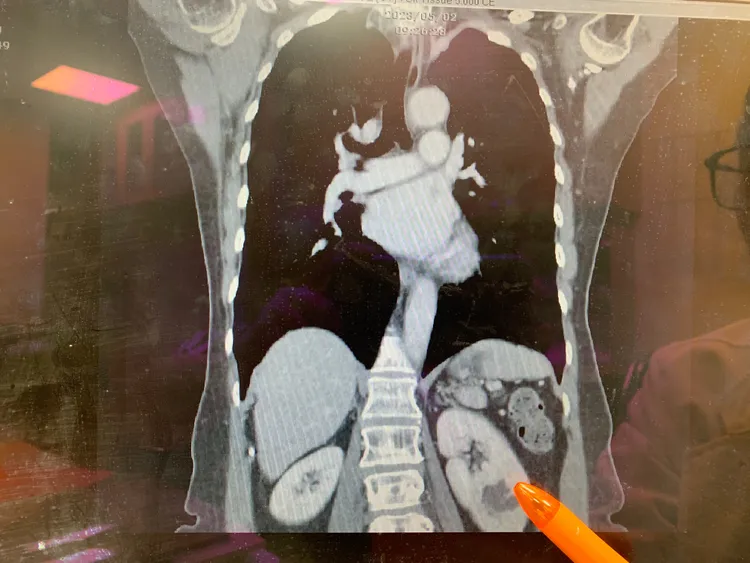

衛福部台中醫院泌尿科醫師趙浩堅指出,患者是在例行性健檢時發現左側輸尿管有顆1.2公分結石合併泌尿道感染,超音波發現左側有腎臟水腫狀況,進一步電腦斷層檢查,竟發現患者左側有2顆腎臟跟兩條完整的輸尿管,即臨床所稱「單側雙套集尿系統」。

趙浩堅醫師說,有3顆腎臟的人腎功能沒比較好,泌尿道感染與尿液逆流機率反而比正常人高。台中醫院提供

「單側雙套集尿系統」在臨床上並不少見,發生率從百分之一到千分之八不等。台中醫院提供